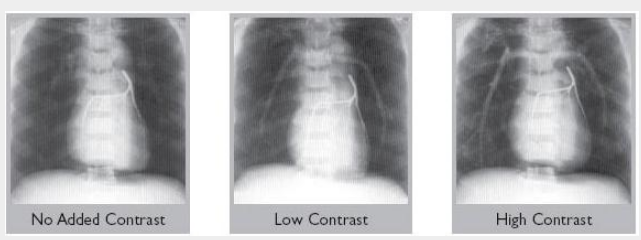

All models are available with blood-equivalent pulmonary arteries, or with low or high contrast media added.

提供血液當(dāng)量肺動脈,或添加低或高對比劑。